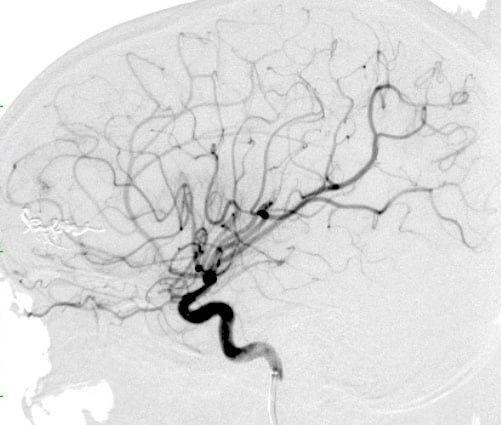

Συγκεκριμένα, η 14χρονη διεκομίσθη στο νοσοκομείο μας από το Γ.Ν.Θ. “Ιπποκράτειο”, την Κυριακή 16 Νοεμβρίου, με ενδοεγκεφαλική αιμορραγία λόγω ρήξεως αρτηριοφλεβικής επικοινωνίας εγκεφάλου. Η μικρή ασθενής εισήχθη στη Μονάδα Εμβολισμού του ΙΔΘ και υποβλήθηκε, άμεσα, σε εμβολισμό με ρευστό εμβολικό υλικό ΟΝΥΧ, από τον Δρ. Βασίλη Κατσαρίδη, MD, PhD Νευροχειρουργό, Ιατρικού Διαβαλκανικού Θεσσαλονίκης. Ο εμβολισμός ολοκληρώθηκε με απόλυτη επιτυχία, με αποτέλεσμα την πλήρη απόφραξη της επικοινωνίας. Μετά το πέρας της επέμβασης, η 14χρονη έλαβε εξιτήριο την ίδια ημέρα, επιστρέφοντας στο Γ.Ν.Θ. “Ιπποκράτειο” σε άριστη γενική και νευρολογική κατάσταση.